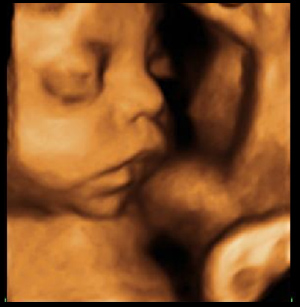

Desarrollo feto semana 31: Le empieza a faltar espacio

Tu bebé ya pesa casi un kilo y medio y mide más de 40 centímetros en la semana 31 de embarazo. Al ser cada vez más grande, el útero empieza a quedarse estrecho. Por eso los movimientos de tu pequeño no son tan numerosos en esta semana de gestación.